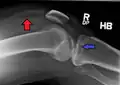

Fractures of the tibial plateau are caused by a varus (inwardly angulating) or valgus (outwardly angulating) force combined with axial loading or weight bearing on knee. The classically described situation in which this occurs is from a car striking a pedestrian's fixed knee (bumper fracture). A bumper fracture is usually a fracture of the lateral tibial plateau, caused by a forced valgus movement. This causes the lateral part of the distal femur and the lateral tibial plateau to come into contact, compressing the tibial plateau and causing the tibia to fracture. The name of the injury is because it was described as being caused by the impact of a car bumper on the lateral side of the knee while the foot is planted on the ground, although this mechanism is only seen in about 25% of tibial plateau fractures.[5] The term "bumper fracture" was coined in 1929 by Cotton and Berg.[6] Fracture of the neck of the fibula may also be found, and associated injury to the medial collateral ligament or cruciate ligaments occurs in about 10% of cases.[7][8]

However, most of these fractures occur from motor vehicle accidents or falls. Injury can be due to a fall from height in which knee forced into valgus or varus. The tibial condyle is crushed or split by the opposing femoral condyle, which remains intact. The knee anatomy provides insight into predicting why certain fracture patterns occur more often than others. The medial plateau is larger and significantly stronger than the lateral plateau. Also, there is a natural valgus or outward angulation alignment to the limb which coupled with the often valgus or outwardly angulating force on impact will injure the lateral side. This explains how 60% of plateau fractures involve the lateral plateau, 15% medial plateau, 25% bicondylar lesions. Partial or complete ligamentous ruptures occur in 15-45%, meniscal lesions in about 5-37% of all tibial plateau fractures.[9]